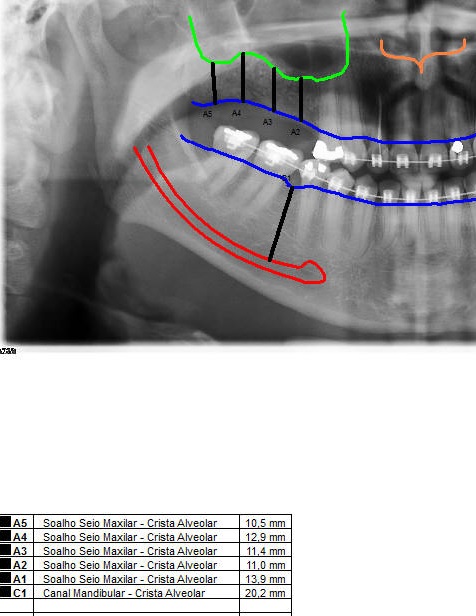

Enxerto de seio maxilar